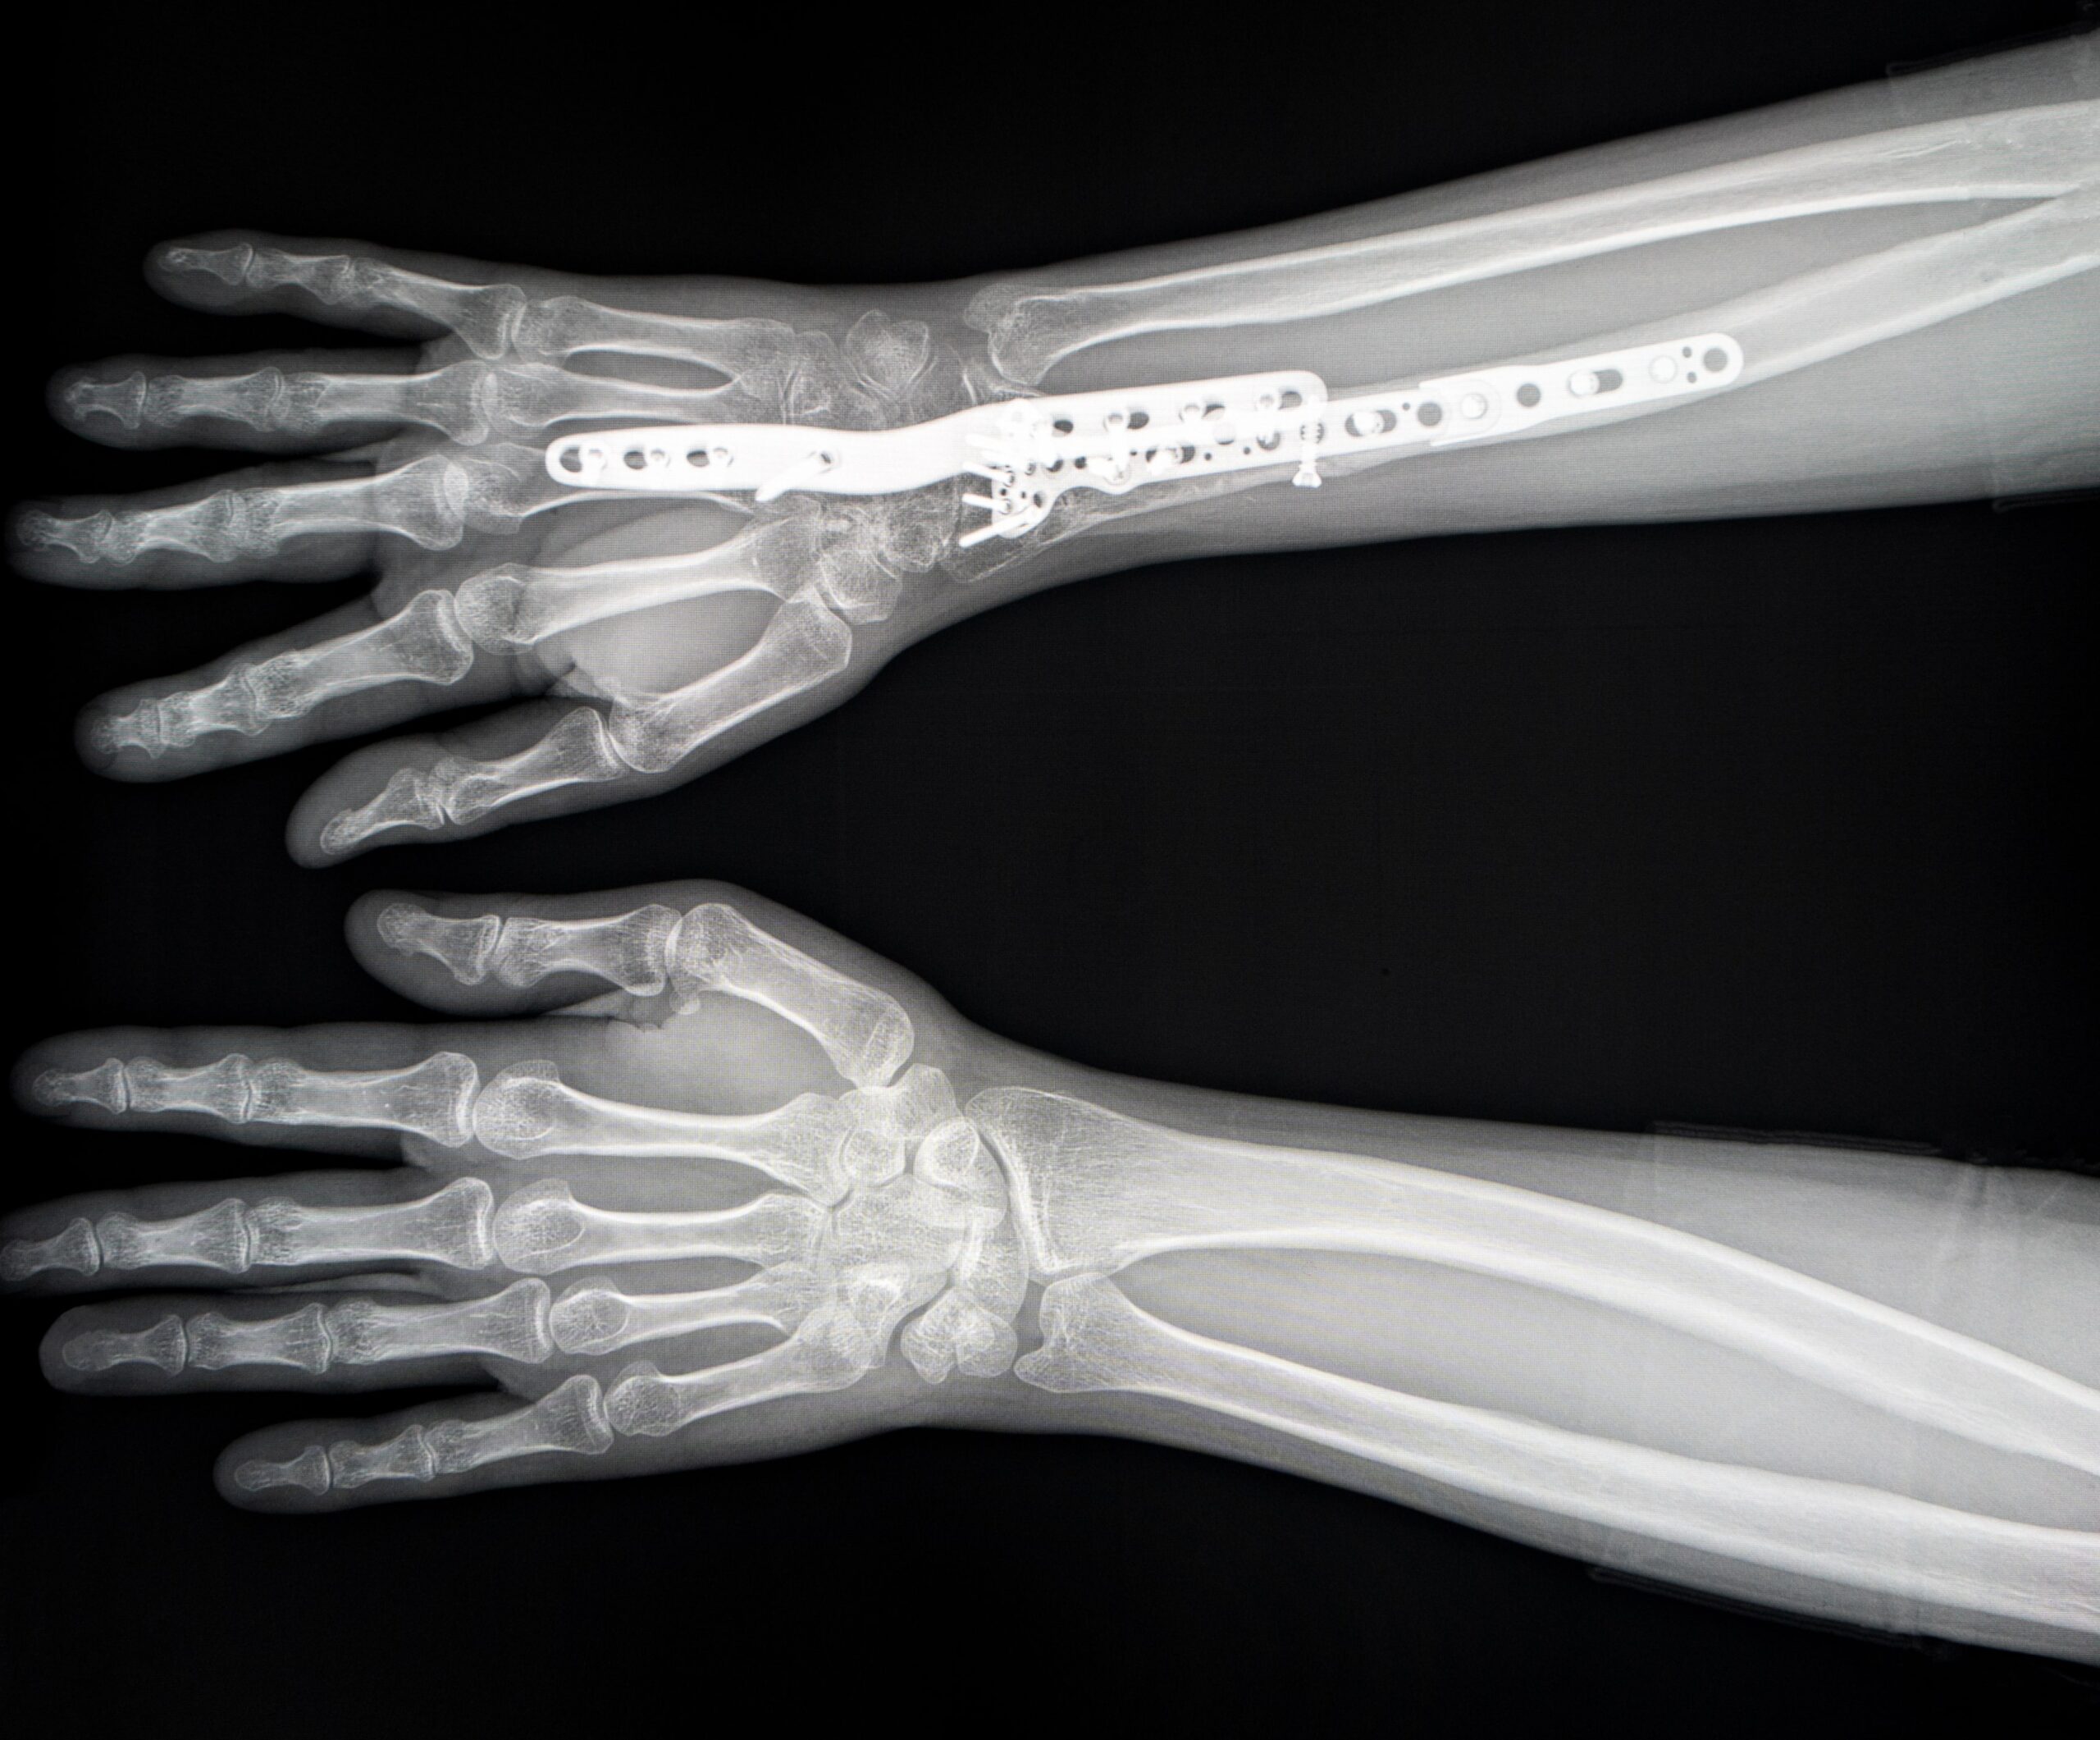

Operativ: Je nach Arthroseform kann eine Teilversteifung (RSL Fusion, Four Corner Fusion) bzw. eine Komplettversteifung (Panarthrodese) des Handgelenks durchgeführt werden

Es erfolgt eine klinische Untersuchung, sowie ein Röntgen, um die Diagnose zu sichern und den Eingriff zu planen. Zudem ist eine Computertomografie notwendig, um die Arthrose zu klassifizieren und mögliche am Röntgen eingeschränkt beurteilbare Abschnitte des Handgelenks genau beurteilen zu können.

Der erste Kontrolltermin findet meist zwei Tage nach der Operation statt, um die Wundheilung und den Behandlungsverlauf zu überprüfen. Weitere Röntgen sind in der Regel nach 2 Wochen (bei Nahtentfernung), nach 6 Wochen, nach 12 Wochen sowie nach 52 Wochen empfohlen.